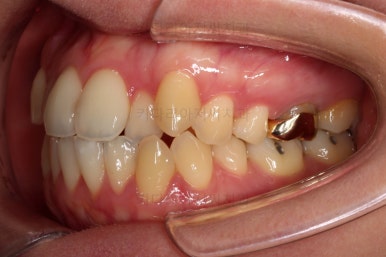

초진 시, 입안의 모습입니다.

좌측 송곳니가 덧니처럼 튀어나가 있고, 송곳니 옆의 작은 억므니가 안으로 쏙 들어가서 덧니 느낌이 더 강조되어 보이네요.

위아래 앞니가 긴밀하게 겹침이 없는 약간의 개방교합(오픈바이트, Openbite) 경향이 보입니다.

옆모습에서 약간의 돌출감이 있으나 힘을 줘서 다물만큼 부자연스러운 양상은 아니여서 돌출에 관해서는 환자분의 취향에 맡기기로 했습니다.